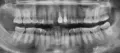

• По данному снимку сложно судить, толи материал выведен за верхушку, толи корень резорбирован. Но, определённо, в области апекса имеется объёмное воспаление, которое необходимо купировать, так как оно будет только нарастать. Возможности решения данной проблемы зависят от картины на КЛКТ.Э, но требуются создание оттока экссудата - по средством перелечивания канала, дренаж или у читать далее